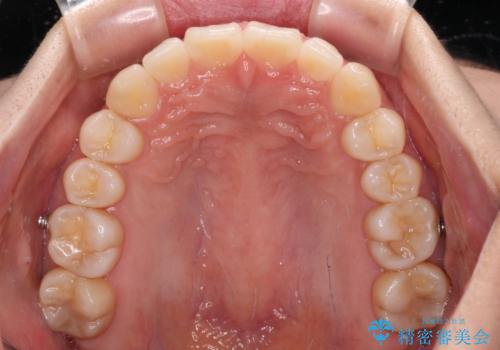

- 上顎前歯の隙間を気にして来院された患者様です。

下顎前歯が上顎前歯に食い込むような咬み合わせにより、上顎前歯が開いてしまっていたため、咬合高径の挙上により突き上げを改善するよう、インビザラインにより矯正治療を行うこととしました。

咬合高径の挙上により上顎前歯の突出感も改善することができ、整った口元となりました。